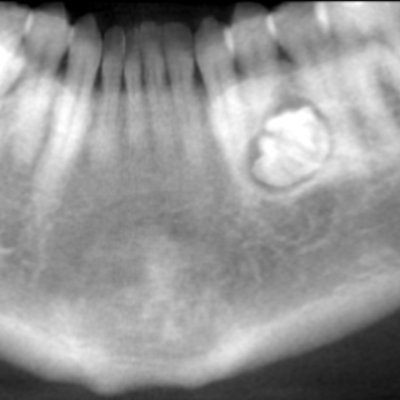

Dr. Juan F. YepesEndodonticsCase #827: 40-year-old woman with lesionA 40-year-old woman was referred to the endodontist by her family dentist to evaluate a lesion located at the periapical area of tooth #30. The woman was asymptomatic. Challenge yourself with this DrBicuspid case study, and put your dental expertise to the test.July 17, 2025X-RayCase #667: 63-year-old man with mandibular lesionA 63-year-old man presented to the oral surgeon after being referred by his family dentist because of an unusual radiolucency at the inferior border of the right mandible. Challenge yourself with this DrBicuspid case study.June 25, 2025Imaging & CAD/CAMCase #787: 32-year-old woman with lesion on the left mandibleA 32-year-old woman was referred to the oral surgeon because of a lesion on her left mandible. The patient was asymptomatic and had no paresthesia or swelling. Challenge yourself with this DrBicuspid case study and put your dental expertise to the test.April 3, 2025Page 1 of 1Top StoriesLegal IssuesMan arrested for torching orthodontics practiceA 62-year-old man was arrested for suspected arson and burglary after he was allegedly found inside an orthodontics practice set ablaze.CardiovascularTime for a dental care protocol for heart transplant patients?Office ManagementShopping for a new credit card processor won't lower your feesPractice SalesChoosing the right adviser for acquiring a dental practiceLegal IssuesMan accused of botched dental procedures sentenced